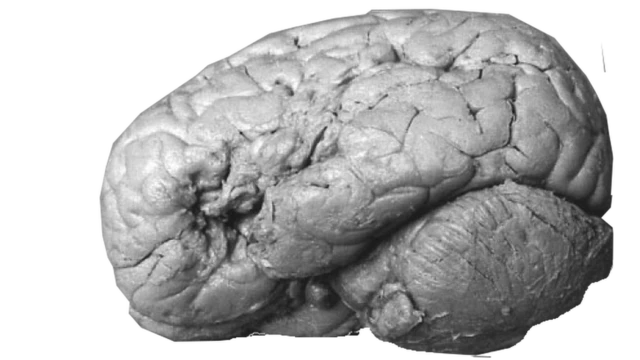

Cuando, a los pocos días de enterarse de su existencia, Tan murió, Broca le hizo una autopsia y comprobó que estaba en lo cierto: encontró tejidos dañados en donde esperaba.

El hallazgo sentó las bases para la neurociencia y la neuropsicología moderna.

Broca se convirtió en una figura célebre en la investigación del cerebro y pasó a la historia de la ciencia.

Todavía hoy, la región que identificó en el lóbulo frontal como el área conectada con el habla se conoce como "área de Broca", y los problemas del habla que se desarrollan a partir de una lesión en esa zona se conoce como "la afasia de Broca".